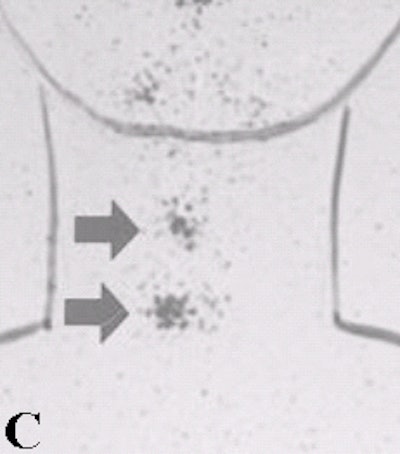

![]() |

Above, an 131I diagnostic scan. Below, a post-therapeutic 131I scan. In these three patients who received 131I therapy the same day as the diagnostic scan, stunned thyroid lesions failed to take up any of the therapeutic dose. Images courtesy of Dr. Hee Myung Park.